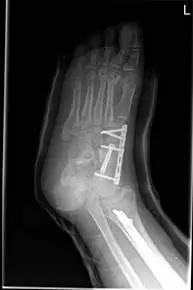

These are pics of an open midfoot fracture and dislocation after a motor vehicle accident.

These are pics of the external fixator on to hold temporary reduction prior to internal fixation